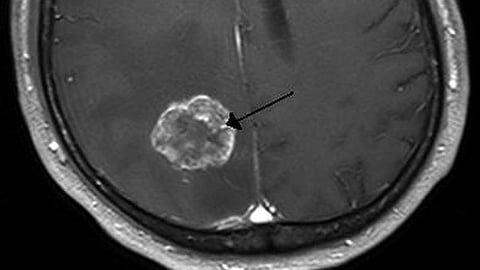

Although early detection of many types of cancer has contributed to the recent increases in cancer survival rates, the survival rate for brain tumors has remained almost unchanged for over 20 years. Partly this is due to their late detection. Physicians often discover brain tumors only after the onset of neurological symptoms, such as loss of movement or speech, by which time the tumor has reached a considerable size. Detecting the tumor when it is still small, and starting treatment as soon as possible. should help to save lives.

One possible sign that a person has a brain tumor is the presence of tumor-related extracellular vesicles (EVs) in their urine. EVs are nano-sized vesicles involved in a variety of functions, including cell-to-cell communication. Because those found in brain cancer patients have specific types of RNA and membrane proteins, they could be used to detect the presence of cancer and its progression.